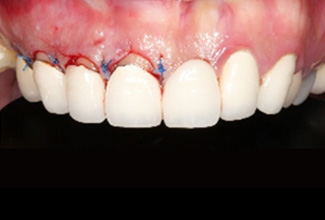

右側前牙進行牙冠增長術,調整牙齒比例。

左側側門牙進行牙肉增生手術,解決牙齦萎縮問題。